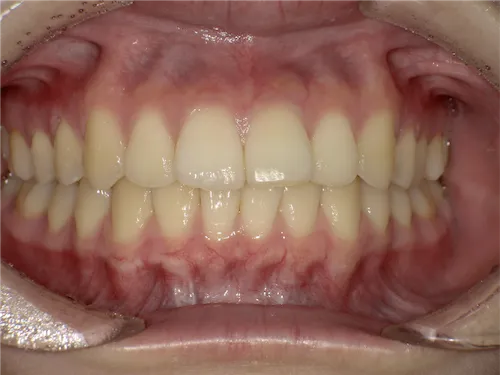

歯科の医療ホワイトニング

痛くない・しみないのに、45分で白くなる。